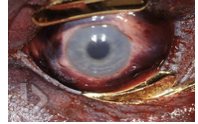

face and neck are deep purple from congestion; petechiae of conjunctiva and sclera, confluent scleral hemorrhage

cyanosis, petechial hemorrhages of conjunctiva, sclera and periorbital skin

blood gets to head but can’t drain = congested face, numerous petechiae of sclera and conjunctiva, periorbital and face skin too

congestion of face, petechial hemorrhages, fingernail marks, hemorrhage in the strap muscles, hyoid fracture, abrasions/contusions on neck

icteric sclera